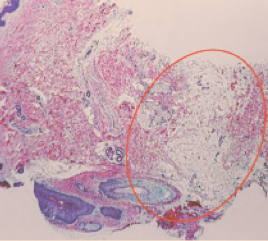

Эффект от процедуры длится всю жизнь, это связано с тем, что онтогенез потовых желез проходит только в эмбриональном периоде, так что они не регенерируют после рождения (рис. 6; Hai-Hong Li et al. 2006).

Рис.6(a). Данные гистологии. Эккриновые и апокриновые железы до процедуры.

лечение гипергидроза на аппарате MiraDry

Рис.6(b). Данные гистологии. Завершенные некроз желез спустя 10 дней после процедуры.

Рис.6(c). Данные гистологии. Отсутствие потовых желез через 6 месяцев после первой процедуры.